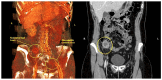

Cervical cancer is the fourth most common cancer in women, the highest mortality being found in low- and middle-income countries. Abdominal parietal metastases in cervical cancer are a very rare entity, with an incidence of 0.1-1.3%, and represent an unfavorable prognostic factor with the survival rate falling to 17%. Here, we present a review of cases of abdominal parietal metastasis in recent decades, including a new case of a 4.5 cm abdominal parietal metastasis at the site of the scar of the former drain tube 28 months after diagnosis of stage IIB cervical cancer (adenosquamous carcinoma), treated by external radiotherapy with concurrent chemotherapy and intracavitary brachytherapy and subsequent surgery (type B radical hysterectomy). The tumor was resected within oncological limits with the histopathological result of adenosquamous carcinoma. The case study highlights the importance of early detection and appropriate treatment of metastases in patients with cervical cancer. The discussion explores the potential pathways for parietal metastasis and the impact of incomplete surgical procedures on the development of metastases. The conclusion emphasizes the poor prognosis associated with this type of metastasis in cervical cancer patients and the potential benefits of surgical resection associated with systemic therapy in improving survival rates.